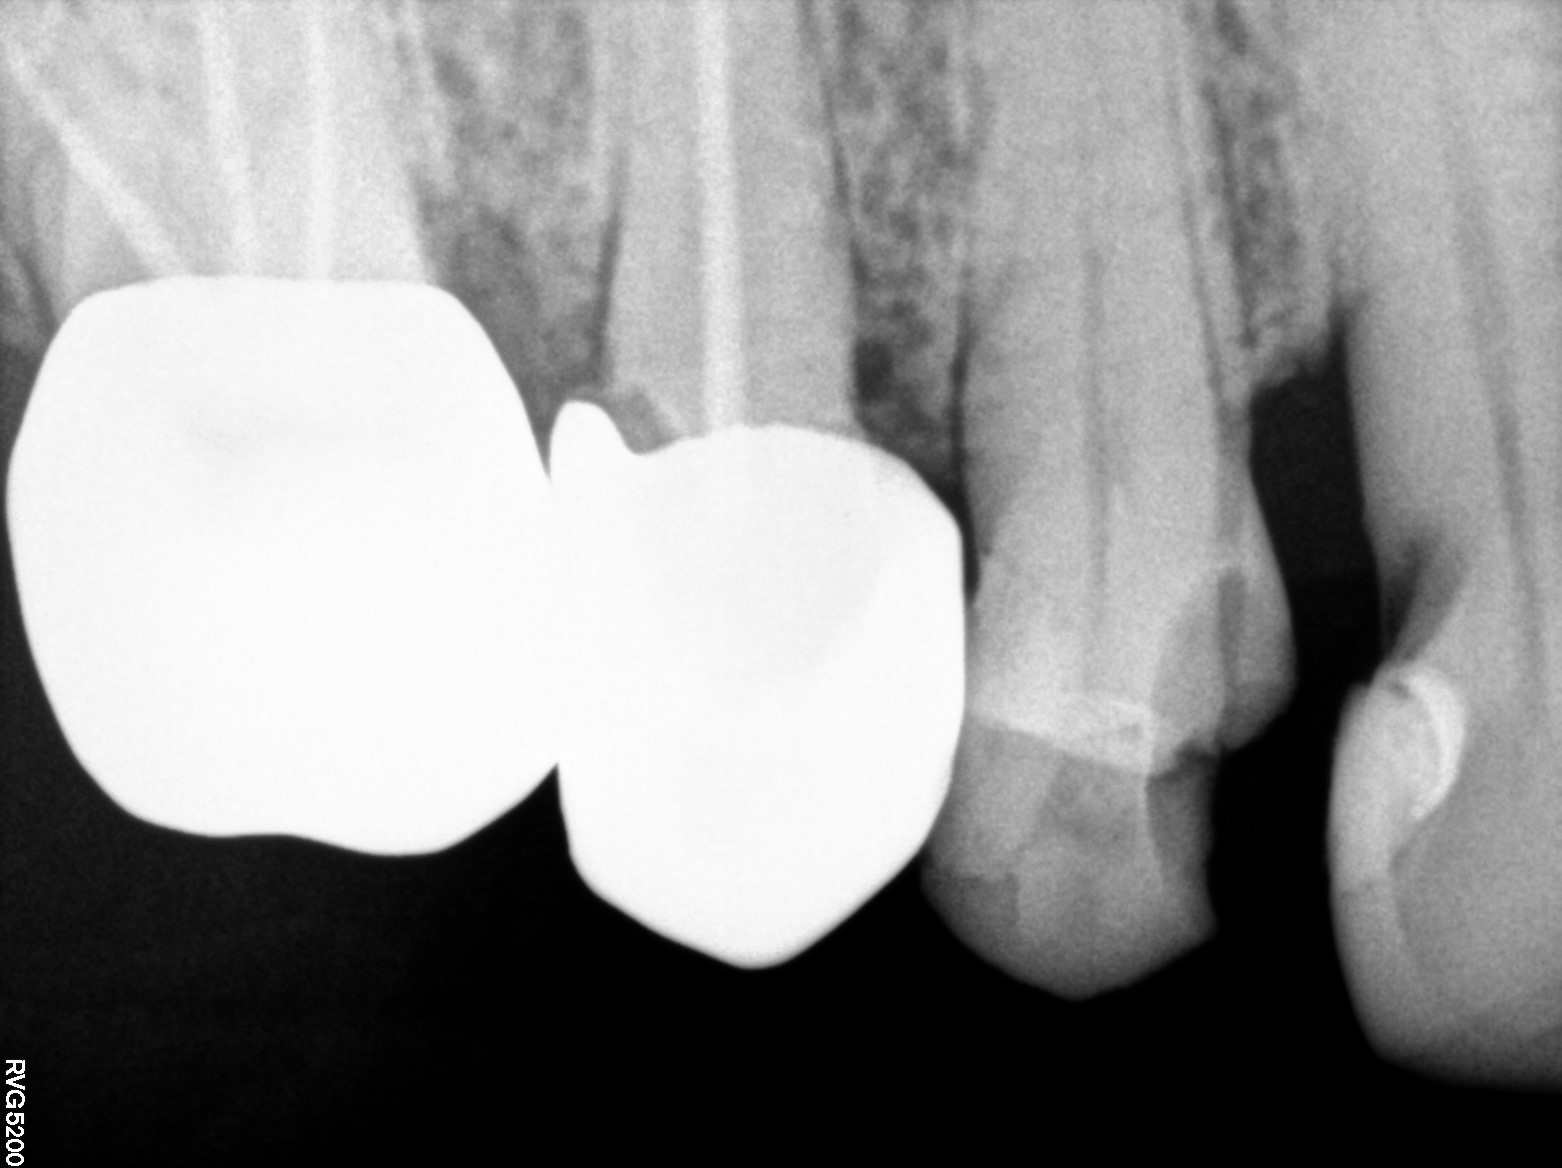

Dental Radiographs FHIR: DocumentReference · LOINC 24641-7

d (12).jpg

24641-7